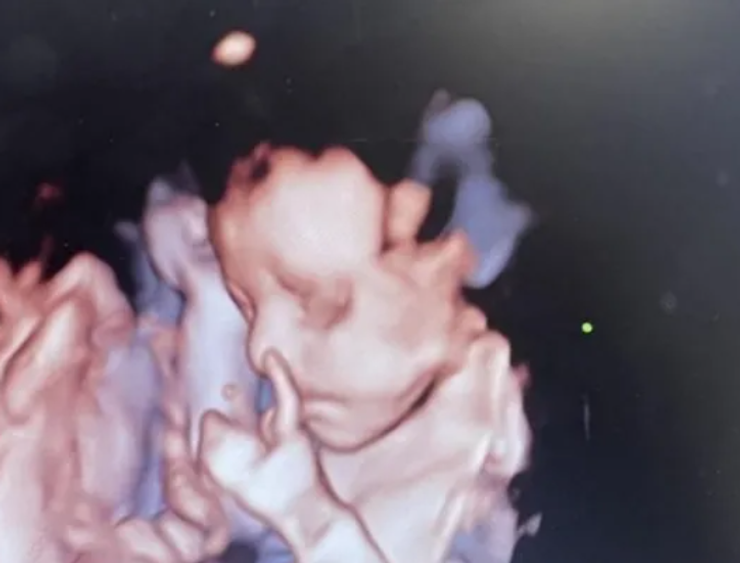

Мэдди Лундстрам на 25 неделе беременности сделала УЗИ | Фото: SWNS

20-летняя мать-одиночка Мэдди Лундстрам из городка Конви (Великобритания) рассмеялась, когда во время УЗИ на 25-й неделе беременности увидела на экране жест, который показала в утробе ее дочь. Об этом пишет издание Metro.

Чтобы окончательно убедиться, что рисков для жизни и здоровья нет, британка обратилась в частную клинику. Ее удивлению не было предела, когда во время очередного УЗИ малышка выставил пальчики вверх, как будто отмахиваясь от матери, которая не дает ей покоя.

"Она сначала не смотрела в камеру, а потом через несколько секунд уже поднимала пальцы вверх, будто сказала: "Я в порядке — уходи", — вспоминает тот курьезный инцидент мать.